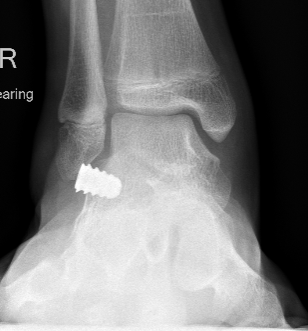

Subtalar arthroeresis

implantimplantimplant

Concept

Sinus tarsi implants limit excessive pronation

Endosinotarsal - implant in the sinus tarsi

Exosinotarsal - screw external to the sinus tarsi